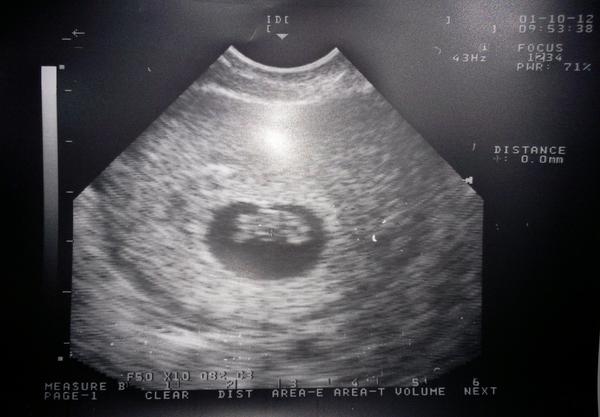

Jinak asi mi chtěla udělat radost. Myslím, že dává průkajdu tak v 9-10tt a prenatal box jsem viděla, že dávala jedné mamině, když byla poprvé na ozvech, ale asi je to jedno a individuální. Dívala se i na utz z minulého těhu ze stejné doby a zdálo se jí, že tenkrát to bylo menší a i to místo ve kterém je mimčo bylo menší, byla to taková slza jakoby. Tak teď to prej vypadá v pořádku.